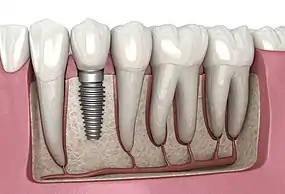

A titanium dental implant with a crown attached used for a single tooth replacement

Dental Implant, 3D Illustration

A dental implant (also known as an endosseous implant or fixture) is a prosthesis that interfaces with the bone of the jaw or skull to support a dental prosthesis such as a crown, bridge, denture, or facial prosthesis or to act as an orthodontic anchor. The basis for modern dental implants is a biological process called osseointegration, in which materials such as titanium or zirconia form an intimate bond to the bone. The implant fixture is first placed so that it is likely to osseointegrate, then a dental prosthetic is added. A variable amount of healing time is required for osseointegration before either the dental prosthetic (a tooth, bridge, or denture) is attached to the implant or an abutment is placed which will hold a dental prosthetic/crown.